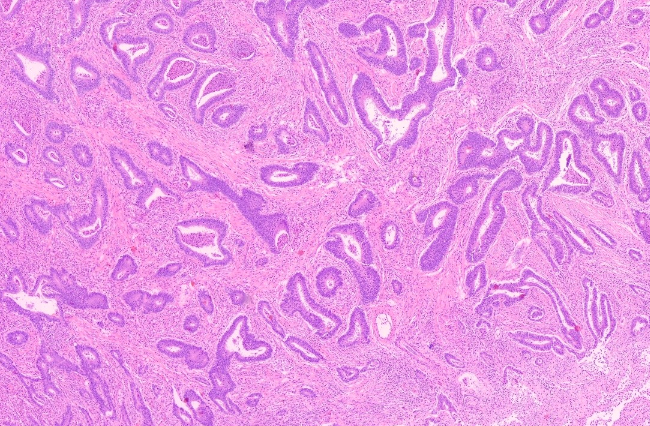

Ein Adenom kann sich unter umständen zu einem bösartigen Tumor entwickeln. Tritt dieser Fall ein, handelt es sich um ein Karzinom, welches in Abbildung 3 zu sehen ist. Im Vergleich zum Adenom, ist die Abgrenzung des Karzinoms zum Umliegenden Gewebe abschnittsweise nicht mehr möglich, da es bei dem Tumor zu einer infiltrieren und zerstören des umliegenden Gewebes kommt.